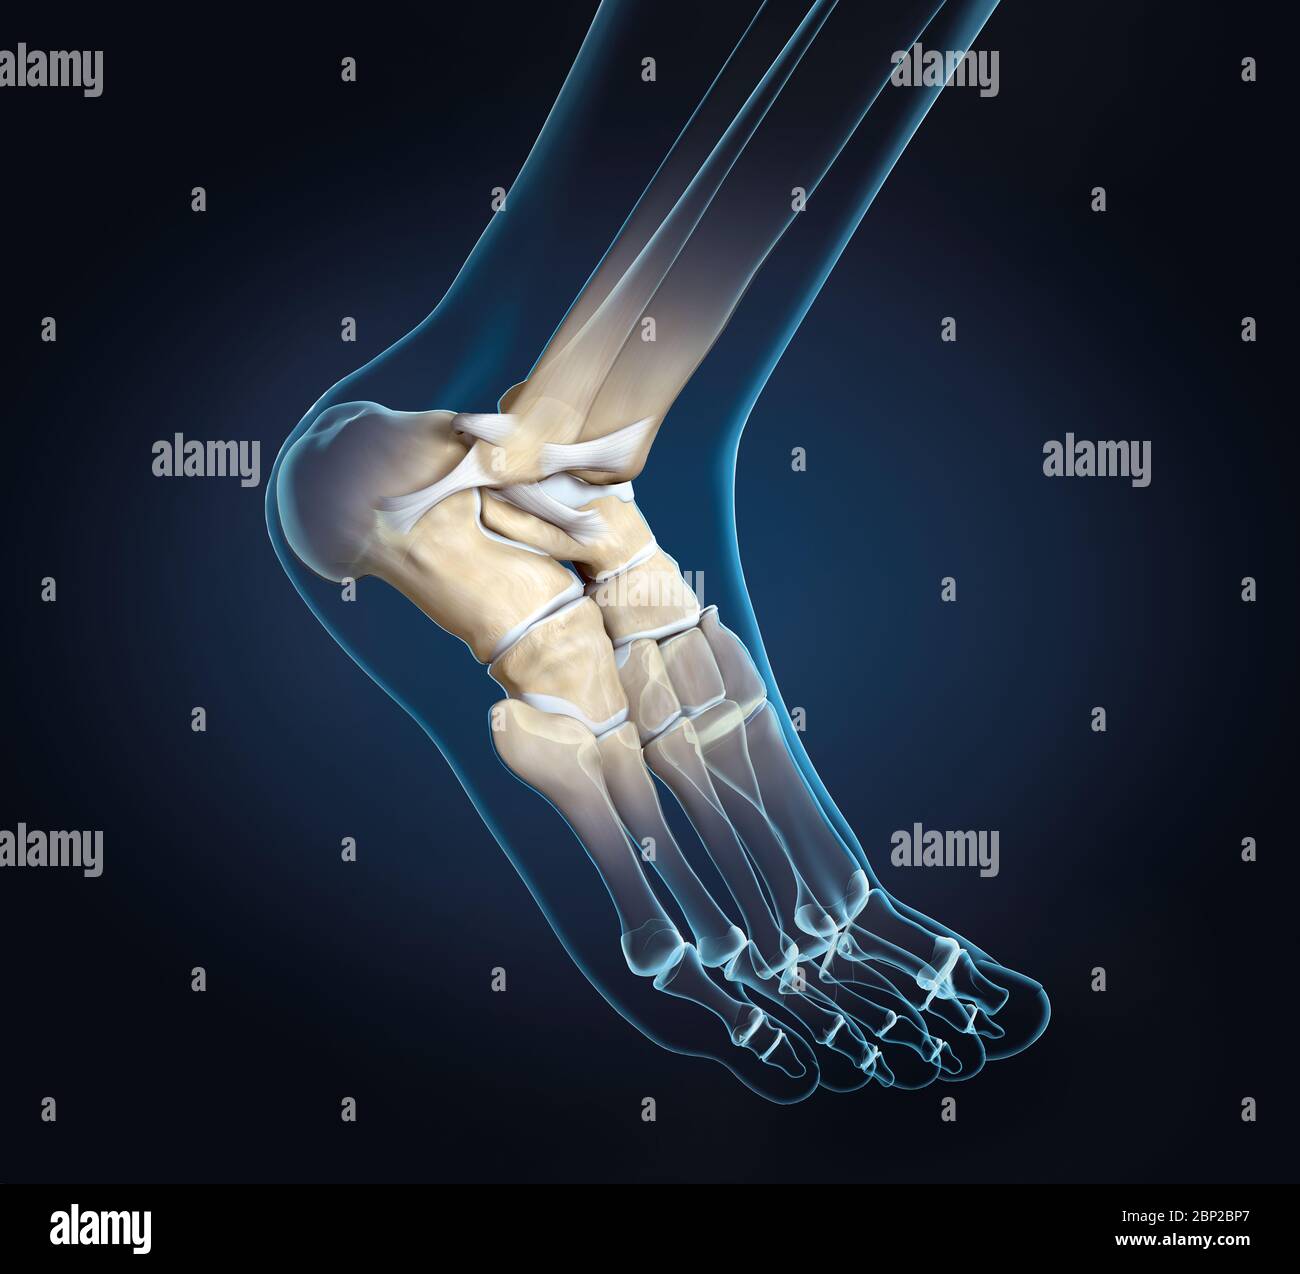

3D illustration showing of a ankle joint with bones, ligaments and articular capsule Stock Photohttps://www.alamy.com/image-license-details/?v=1https://www.alamy.com/3d-illustration-showing-of-a-ankle-joint-with-bones-ligaments-and-articular-capsule-image357782943.html

3D illustration showing of a ankle joint with bones, ligaments and articular capsule Stock Photohttps://www.alamy.com/image-license-details/?v=1https://www.alamy.com/3d-illustration-showing-of-a-ankle-joint-with-bones-ligaments-and-articular-capsule-image357782943.htmlRF2BP2BP7–3D illustration showing of a ankle joint with bones, ligaments and articular capsule